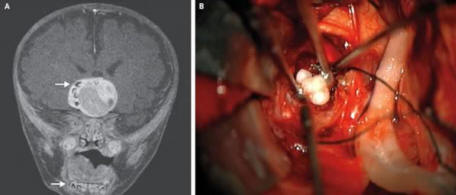

4. Vzácným nádorem v mozku dítěte se ukázal být zub

Maryland 4měsíční dítě může být první člověk, který měl v mozku nádor, který se ukázal být zubem. Poprvé doktoři měli podezření, že se něco stalo, když se zdála hlava dítěte začal růst rychleji, než je charakteristické pro děti jeho věku.

Skenování mozku odhalilo nádor, který obsahoval struktury velmi připomínající lidské zuby, obvykle nalezené v dolní čelisti. Nádor byl odstraněn a nyní se chlapec cítí sebe dobře.